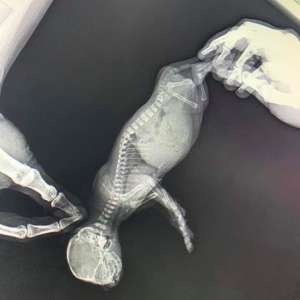

"Я испугалась, что у моего котенка странное вздутие живота и поэтому повезла его в клинику. Доктор его проверил, и сказал, что он просто пухленький".